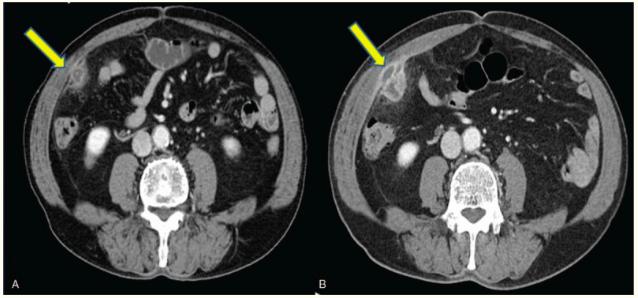

吞食牙签引起肠穿孔致腹腔脓肿

图片尺寸638x298